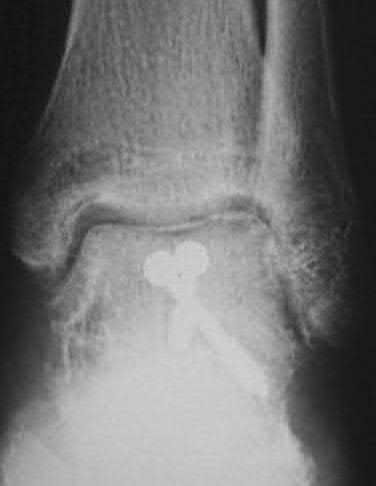

A 25-year-old male sustains an ankle fracture dislocation and undergoes open reduction and internal fixation. He returns to clinic five months following surgery complaining of continued ankle pain and instability with weight bearing. His immediate post-operative AP radiograph is seen in Figure A. Which of the following could have prevented this patient from developing persistent pain?

1) Deep deltoid ligament repair

2) Quadricortical syndesmotic screw fixation

3) Restoration of fibular length and rotation

4) Lateral collateral ligament complex repair

5) Use of two syndesmotic screws

The patient presents with continued ankle pain and instability following open reduction and internal fixation. The radiograph in figure A demonstrates inadequate restoration of fibular length, likely leading to continued tibiotalar instability.

Illustration A demonstrates fibular malreduction with dislocation of the fibula anterior to the tibial incisura. Illustration B shows a comminuted fibula fracture along with a measurement of length from an intact fibula. The arc from the lateral process of the talus to the peroneal groove of the distal fibula is known as the "dime" sign and should remain unbroken if fibular length has been restored. Illustration C demonstrates the use of a push-pull screw and lamina spreader to regain length intraoperatively for a comminuted fibula fracture.

Chu and Weiner review management of malunions of the distal fibula. The authors state that restoration of fibular length, alignment and rotation leads to reduction of the talus, provides a buttress to talar motion in the setting of an incompetent deltoid, and allows the syndesmotic ligaments to heal at the appropriate tension.